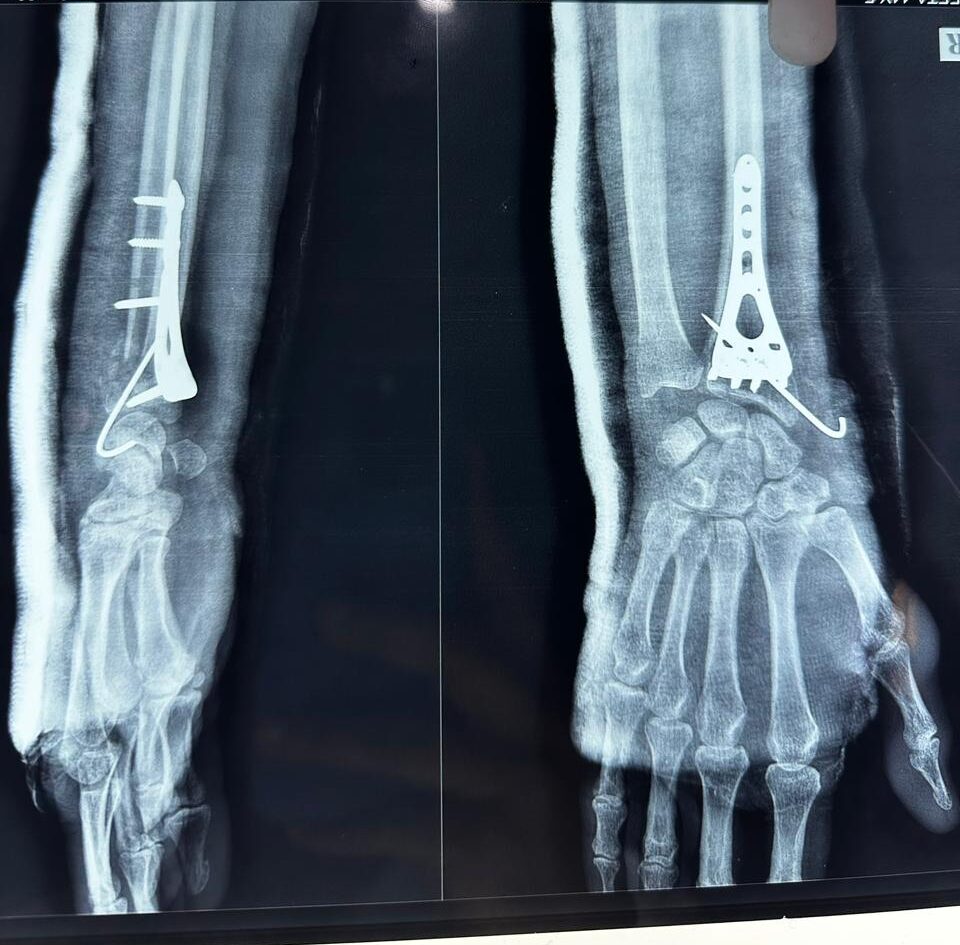

Moments That Mark Meaningful Recovery

Witness real patient transformations at The Ortho Clinic through images that reflect successful treatments and restored mobility.